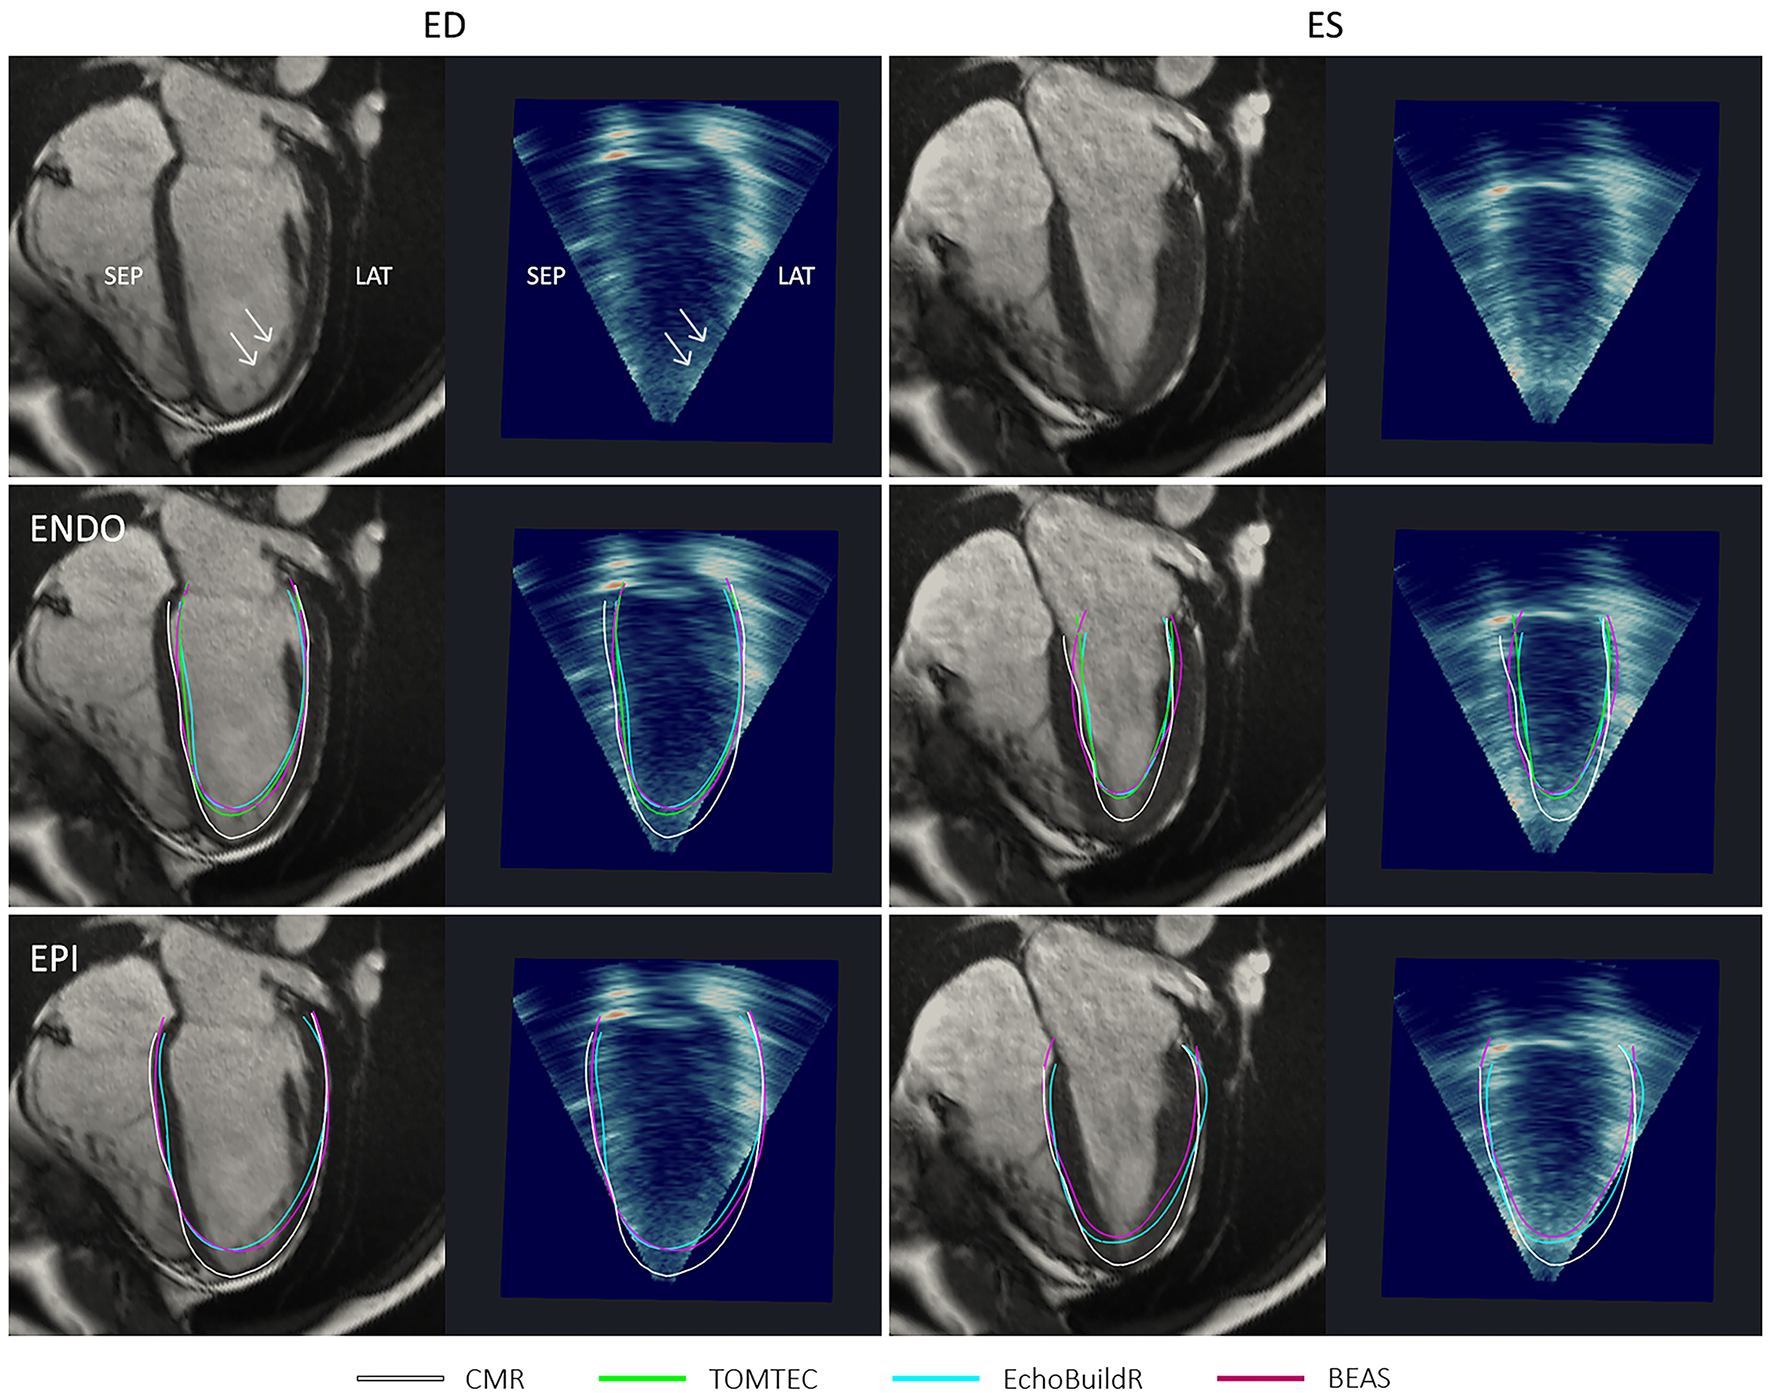

Figure 6

Short-axis CMR slice and corresponding resliced 3D-echo image at end-diastole (ED) and end-systole (ES) for a patient with hypertrophied myocardium. Top row shows endocardial (ENDO) contours, and bottom row shows epicardial (EPI) contours derived using each method indicated in the legend. ANT, anterior; LAT, lateral; SEP, septal; INF, inferior.

In the long-axis views, further discrepancies between 3D-echo and CMR myocardial contours were noted near the apex (Figure 7). On CMR images, apical trabeculations appeared as slight shadows, which could be distinguished from the myocardium. This distinction was less apparent on 3D-echo, leading to the illusion of a foreshortened apex. In addition to the absence of a clear apical endocardium, the apical epicardium was also obscured by its proximity to the thoracic wall. It was further observed that the LV cavity on 3D-echo appeared to be under-segmented at the inferior septum despite (and perhaps in part due to) the particularly bright signal, albeit to a lesser extent than that observed at the inferolateral wall.

Four-chamber long-axis views by CMR and resliced 3D-echo from a healthy participant, at end-diastole (ED) and end-systole (ES). Top row indicates (with arrows) positions and appearances of apical trabeculations in each modality. Middle row shows endocardial (ENDO) contours, and bottom row shows epicardial (EPI) contours derived using each method indicated in the legend. ANT, anterior; LAT, lateral; SEP, septal; INF, inferior.

In areas with signal dropout or low tissue contrast, a larger discrepancy was observed between 3D-echo and CMR (as well as between the three 3D-echo image analyses). Additionally, the appearances of trabeculae at the LV lateral wall were often indistinguishable from the myocardium on 3D-echo—an effect that was more pronounced in the presence of LV hypertrophy (Figure 6). This effect also seemed to impact acquisition, whereby internal wall structures were mistaken for ventricular myocardium, resulting in the inadvertent exclusion of hypertrophied myocardium from the chosen FOV.

At ES, there were larger variations between the endocardial surfaces generated using the three 3D-echo segmentation methods, although underestimation at the apex was still typically observed. Visually, there was no clear trend as to whether 3D-echo analyses were more likely to over or under-segment the LV cavity at ES.